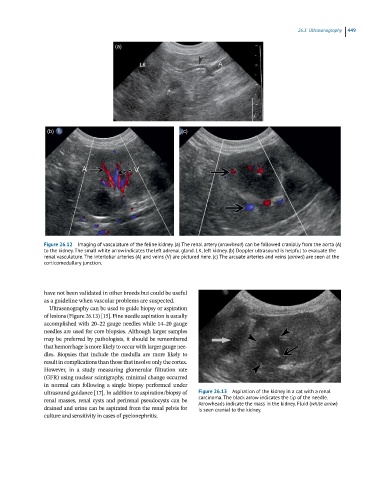

Figure 26.12 Imaging of vasculature of the feline kidney. (a) The renal artery (arrowhead) can be followed cranially from the aorta (A)

to the kidney. The small white arrow indicates the left adrenal gland. LK, left kidney. (b) Doppler ultrasound is helpful to evaluate the

renal vasculature. The interlobar arteries (A) and veins (V) are pictured here. (c) The arcuate arteries and veins (arrows) are seen at the

corticomedullary junction.